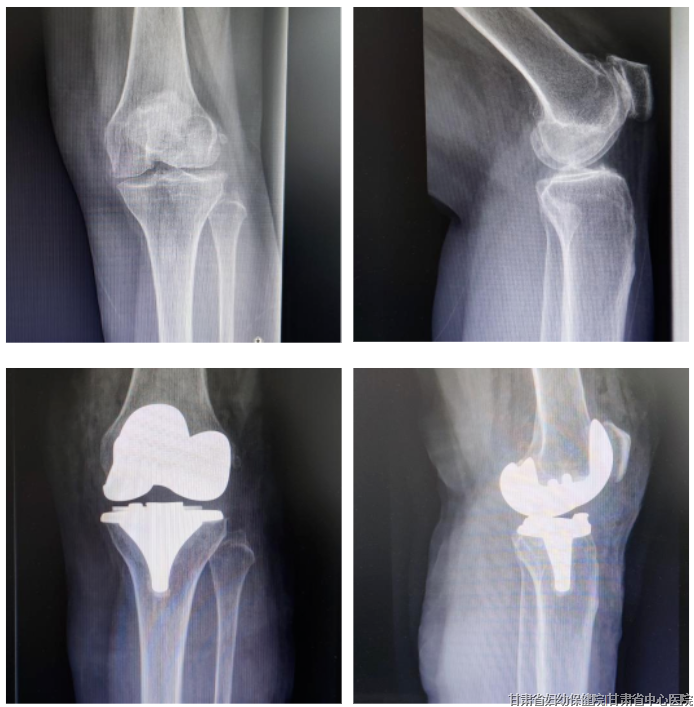

03 术后疼痛别死扛,舒适度过围术期

甘肃省中心医院骨科一名患者在膝关节假体置换术后疼痛剧烈,严重影响了功能锻炼,治疗团队在围术期进行疼痛管理,患者康复过程疼痛评分极低。

不仅如此,对于骨科患者围术期管理,目前加速康复外科(enhanced recovery after surgery, ERAS) 理念中无痛原则贯彻始终,尤其对于急性术后疼痛的控制。急性术后疼痛(acute postoperative pain, APP)主要集中在术后24~72 h, 常持续4~6 d。目前预防和治疗APP的方法不断改善,但仍有超过80%的患者在术后7 d内经历疼痛,其中39%的患者经历“严重”到“极端”的术后疼痛。术后严重疼痛常引发一系列应激反应,升高心血管、呼吸系统并发症和血栓栓塞等并发症的发生率,影响患者免疫功能、消化系统功能、内分泌代谢功能等,严重影响患者术后生活质量。而疼痛控制的及时介入将很大程度缓解此类并发症的发生。